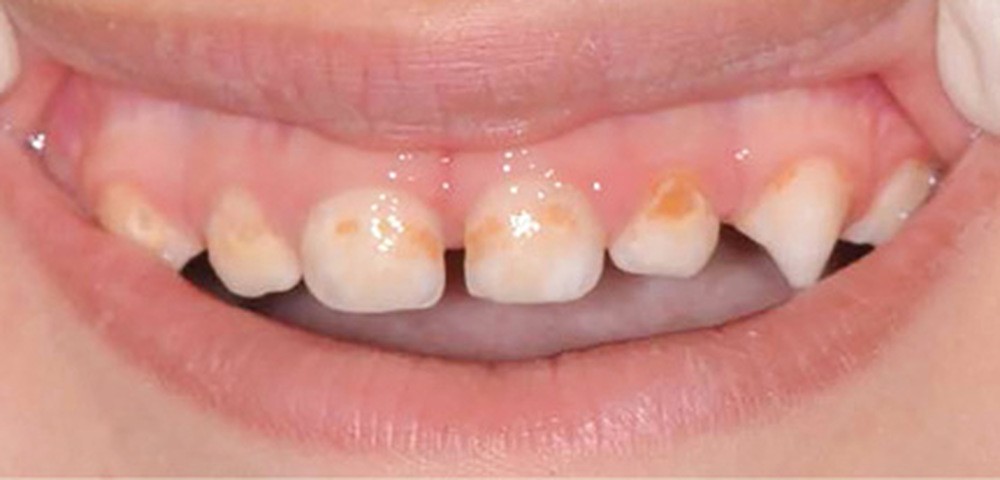

- L’évolution de la maladie carieuse : cette pathologie bactérienne, multifactorielle, se transmet très vite d’une dent à une autre dans la cavité orale de l’enfant. Ainsi, avant l’âge de 6 ans, la carie précoce de l’enfant (CPE) peut atteindre un stade sévère et ne plus permettre à l’enfant de mastiquer sans douleur (fig. 2).

- La perte de chance pour le développement : la CPE non traitée va entraîner l’avulsion précoce de certaines dents, induisant des troubles alimentaires pouvant se répercuter sur le développement général de l’enfant (croissance et développement cognitif), voire de sa vie sociale (absences scolaires répétées, pas de sourire). La CPE a un impact négatif sur la qualité de vie de l’enfant.